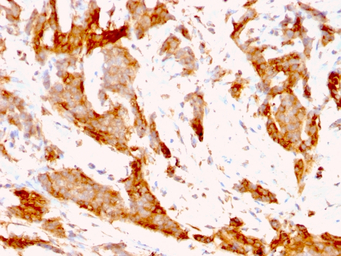

IHC-P analysis of human breast carcinoma tissue using GTX34771 GRP94 antibody [9G10.F8.2].